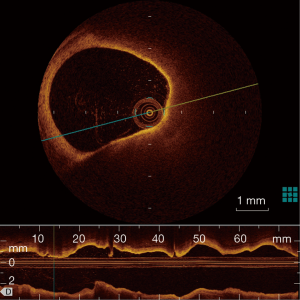

OCT has been used initially in ophthalmology and is now clinically available in cardiology. Compared with IVUS, OCT offers more precise assessment of coronary plaques, utilizing a 10-time greater resolution than that of IVUS (a spatial resolution of 10 µm axially and 20−40 µm laterally). OCT enables the visualization of several important plaque features assisting in determining plaque vulnerability: TCFA, plaque rupture, plaque erosion, lipid core, micro-calcification and neo-vascularization. The description of TCFA incorporates a fibrous cap <70 µm and also requires the arc of the lipid pool to subtend an angle >90 degrees in certain trials as seen in Figure 4. However, there is no strict definition of TCFA and a consensus statement rather ambiguously suggested, OCT-TCFA should reflect the histological definition of a TCFA (61).

Unlike the IVUS studies, there is limited data on the long term predictive value of OCT TCFA lesions as it is a younger technology. A study of 67 patients with OCT showed thinner fibrous cap, larger areas of TCFA and more inflammation was evident on STEMI patients compared to those with SAP (62). Uemura et al. have shown that TCFA and micro-channel images showed a high correlation with subsequent luminal progression (OR: 20.0, P<0.01 for both) (63). Niccoli found MACE occurred more frequently in patients with plaque rupture at the target lesion when compared with those having intact fibrous cap (39.0% vs. 14.0%, P=0.001) in an ACS cohort. Plaque rupture was an independent predictor of outcome on multivariable analysis (OR: 3.74; 95% CI, 1.36−9.74) (64). OCT has been used to follow TCFA and demonstrated an increase in the fibrous cap thickness of patients who were treated with lipid lowering therapy (65).